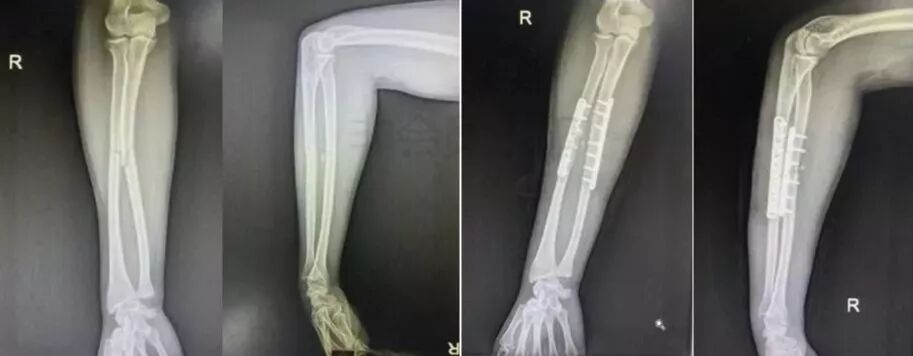

5)前臂骨折(尺骨,桡骨,或双骨折)

图片

• 闭合或开放性骨折均争取伤后6-8h完成。

• 手术后延,尺骨-桡骨骨桥形成风险概率高。

6)桡骨远端骨折

• 绝大部分骨折可以手法复位制动。

• 关节面粉碎,塌陷者应手术。

• 如果伤后拇长伸肌腱卡压,正中神经损伤者,应立即手术。

7)手部骨折

• 无论闭合或开放性骨折,均应早期复位内固定。

• 合并神经,血管,肌腱损伤,紧急手术。